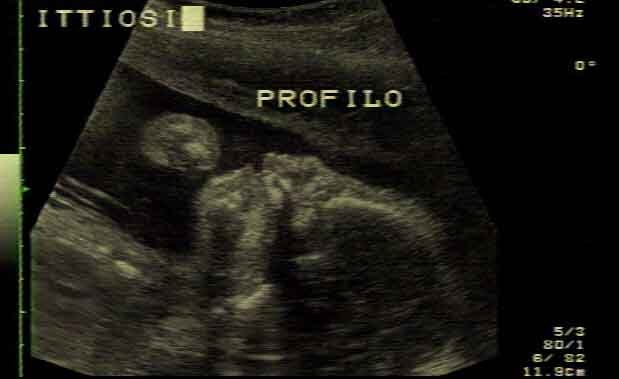

Scrivendo nella rivista Nature Genetics, il team descrive come questo tipo di ittiosi che fa parte delle ARCI porti a una generale desquamazione della pelle diagnosticata alla nascita. Anche se la malattia è rara negli esseri umani, essa si verifica spesso nei golden retriever a causa degli incroci e poiché non è stata contrastata nelle selezione.

Il team ha sfruttato la particolare storia dell’allevamento delle popolazioni di cani per identificare le alterazioni genetiche responsabili della malattia della pelle nei golden retriever. Queste nuove scoperte evidenziano una singola mutazione nel gene PNPLA1, con perfetta segregazione su una modalità di trasmissione recessiva.